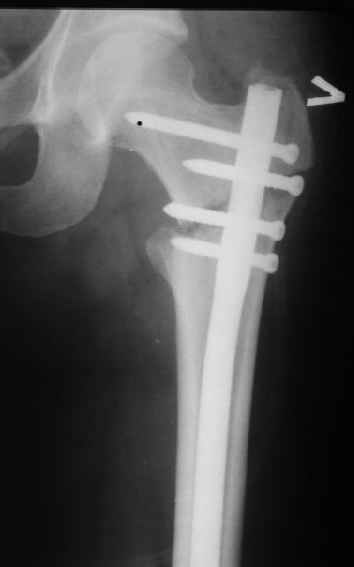

При межвертельных переломах с цефаломедуллярными гвоздями бывает, что проксимальый винт проходит или черед периферический отломок, или прямо над ним. И если остался диастаз, то этот винт при осевой нагрузке не дает сблизиться отломкам. Пример такого остеосинтеза в застарелом случае в приложении.

В качестве предупреждающей меры можно долотом разрушить латеральную стенку дистального отломка под винтом.

В частности, на проксимальном конце сделано еще одно дополнительное статическое отверстие. Можно ввести в проксимальном отделе 4 винта, из них 3 статические (2 в круглые отверстия и 1 по нижнему краю овального). Картинки в приложении. На дистальном конце стержня тоже кое-что улучшено. Спрашивайте в аптеках, как говорится. Выпускается предприятием "ЦИТО" (Москва), то есть это малобюджетное решение.

Конечно, мы не синтезируем остеопорозые вертельные переломы согласно прилагаемому примеру, винты 6 мм вырежутся. Но у более молодых при хорошем качестве кости такие или подобные гвозди с поперечным расположением винтов вполне применимы для меж- и подвертельных переломов.

Картинка красивая, но на мой взгляд, не совсем оптимальная: Слишком медиально введён стержень - риск аваскулярного некроза головки бедра.

вариант межфрагментарного шинирования - зона достаточно простительная т.е. чрезвертельные переломы потенциально хорошо срастаются при любом

расположении сопредельных отломков- хорошая локальная васкуляризация. В приведённом случае я бы предпочёл принцип межфрагментарной компрессии (рекон/гамма нэйл 130- 135) принципу шинирования перелома.

Женя, эта картинка показывает не оптимальное лечение вертельных переломов в моем представлении, а особенности дизайна упомяутого фиксатора.

В частности, его возможности при фиксации переломов проксимального отдела бедра - в сравнении с другими, имеюшими лишь по одному статическому и динамическому отверстию и с кондуктором для введения 2 винтов.

Это было года 2,5 назад, мы тогда еще уточняли возможности шинирования с угловой стабильностью гвоздем с поперечным расположением винтов при переломах проксимального отдела бедра. Пациенту не пришлось приобретать намного более дорогой рекон или проксимальный гвоздь. В приложении еще несколько примеров применения того гвоздя при высоких переломах бедра, в том числе с более латеральной точкой входа. Гвоздь изгибаем для этого.